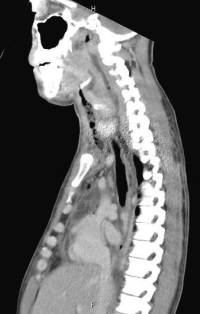

血液所見:赤血球 482 万、白血球 14,500(桿状核好中球 32 %、分葉核好中球 54 %、単球5%、リンパ球9%)、血小板 11 万。血液生化学所見:AST 61 U/L、ALT 69 U/L、尿素窒素 27 mg/dL、クレアチニン 1.2 mg/dL。CRP 36 mg/dL。縦隔条件の頸部CT、胸部CT及び矢状断再構成CTを示す。

治療として適切なのはどれか。2つ選べ。

a. 抗菌薬投与

b. ドレナージ